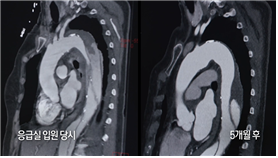

67세 서일윤 씨는 가슴이 찢어질 듯한 통증에 응급실로 향했다. 진단명은 대동맥 박리와 그에 따른 대동맥류. 높아진 혈압이 대동맥의 내벽을 찢어 혈액이 새는 무서운 병이다. 20년 전 고혈압을 진단받았지만, 처방받았던 약 복용을 게을리한 결과였다.

![]() |